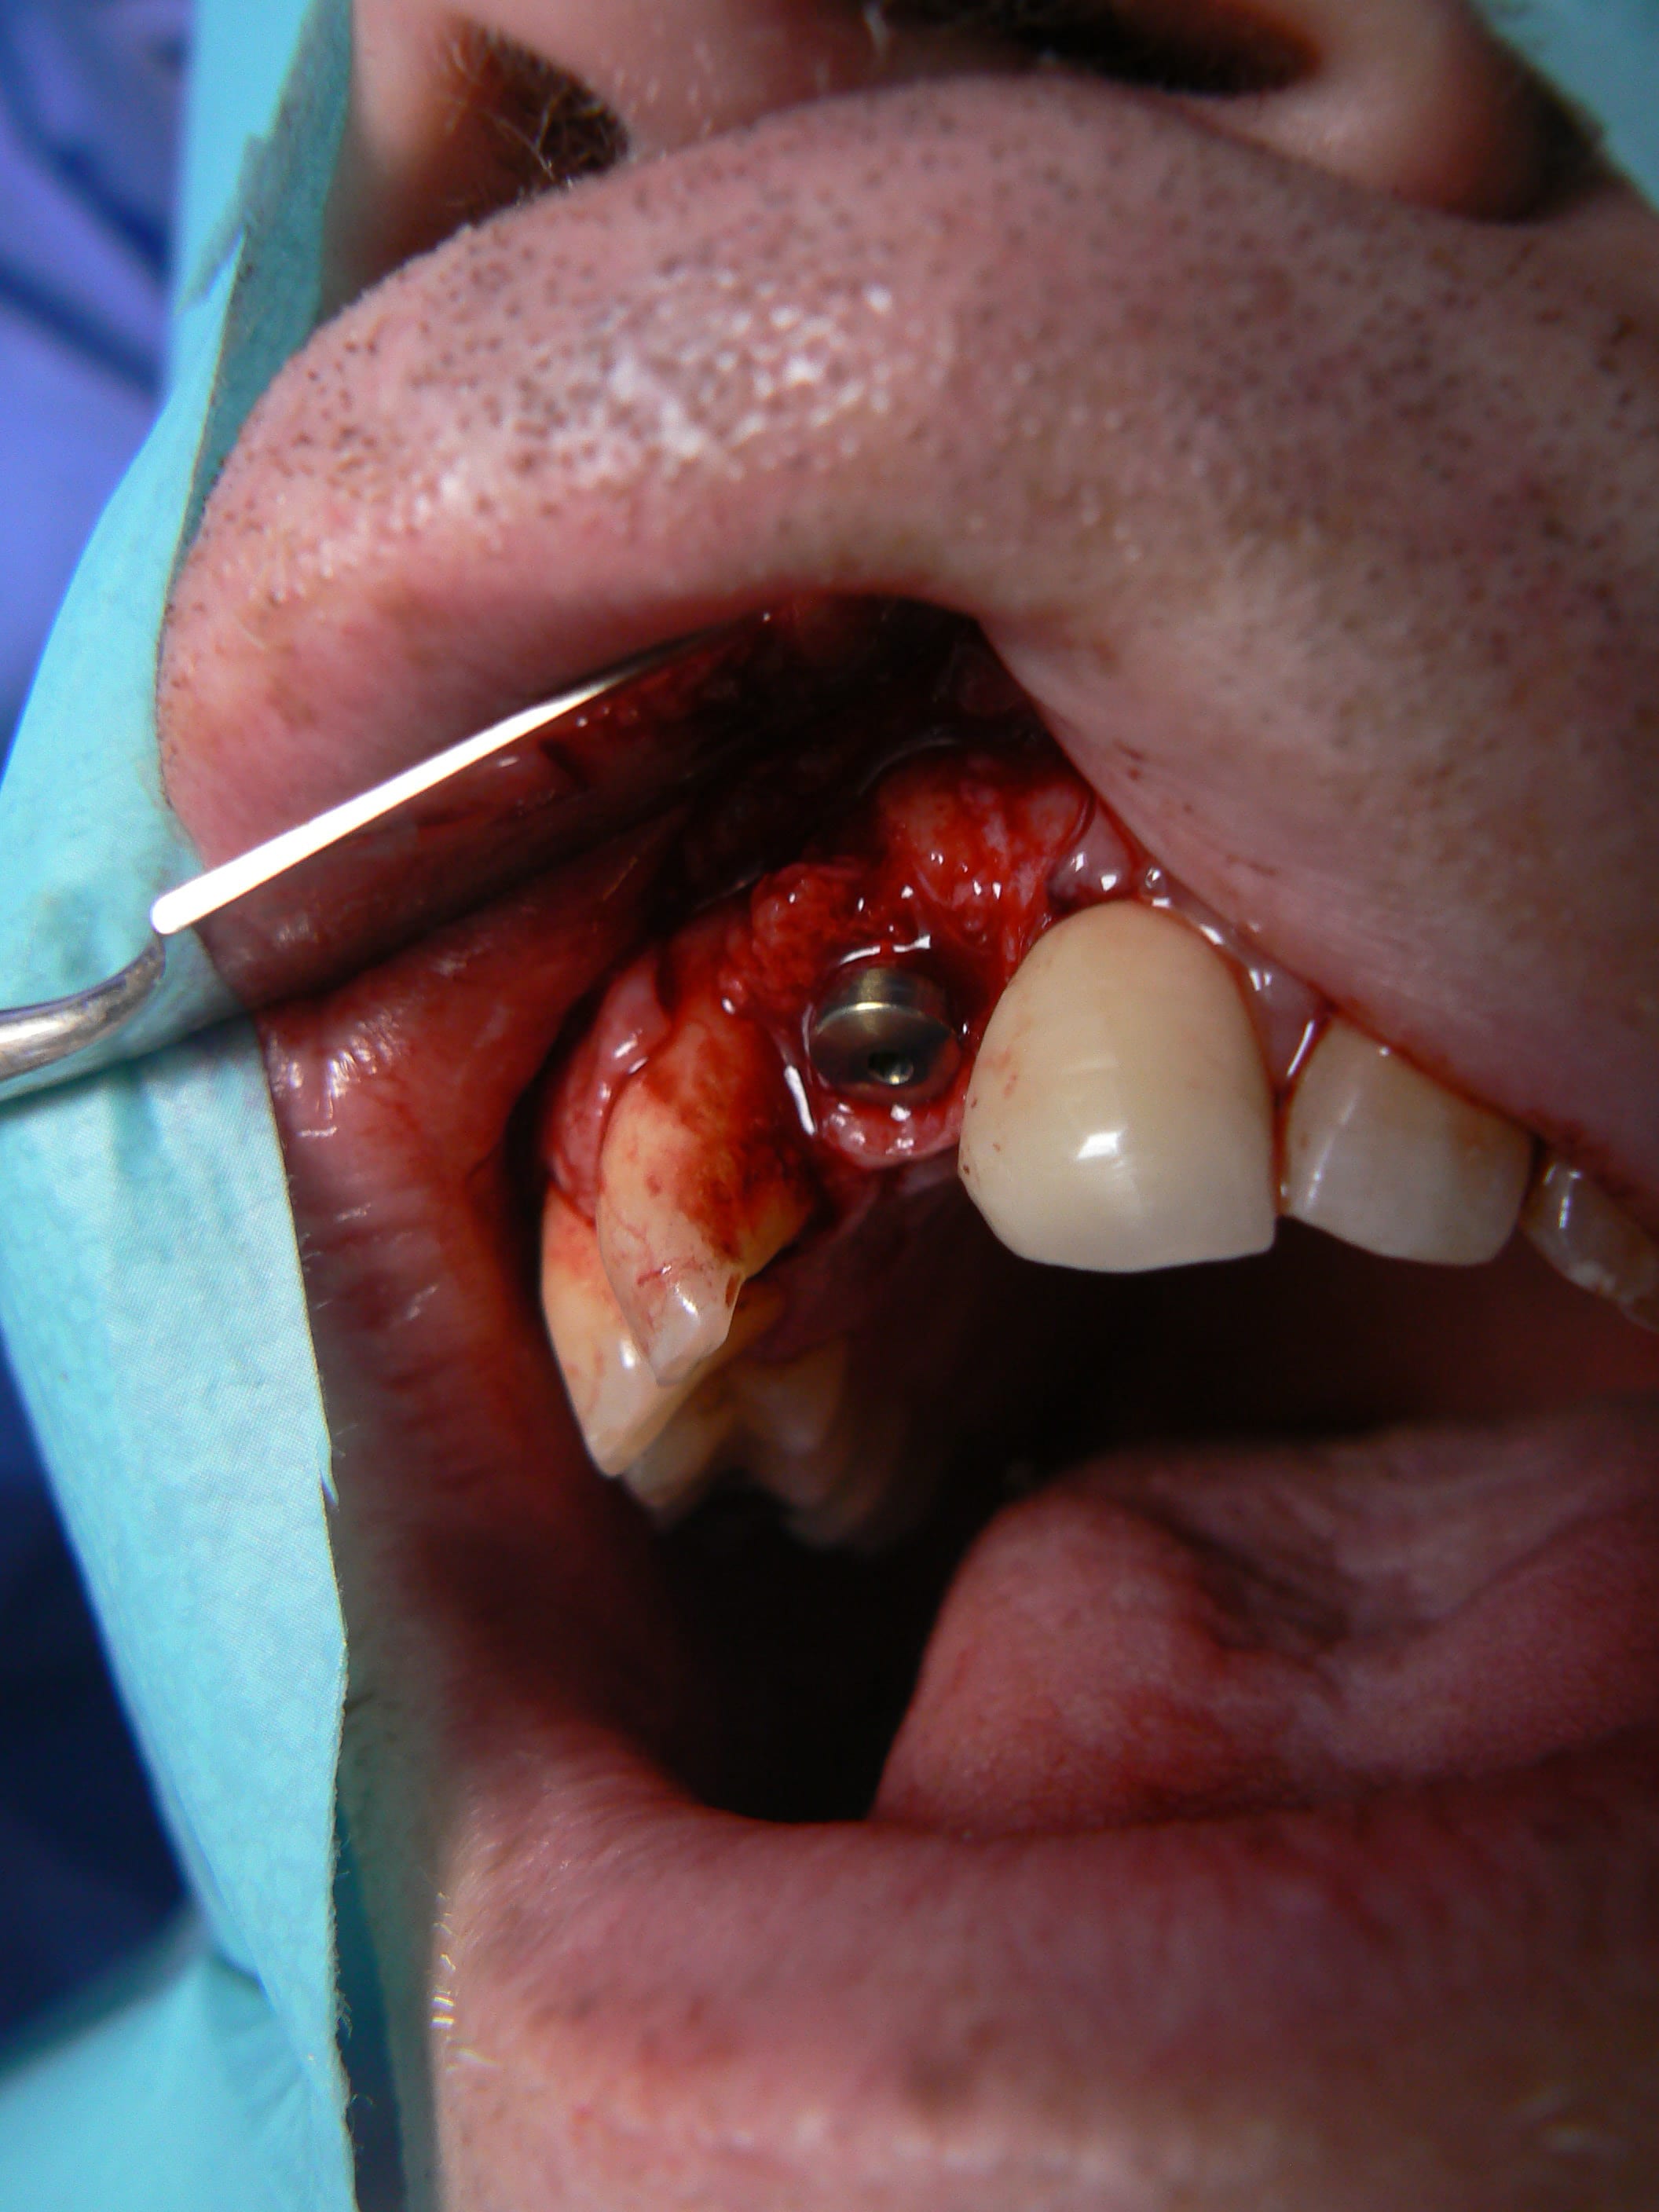

> Ci joint cas avec biobank, très bonne stabilité et consistance a la réouverture

> a 9 mois.

j'ai retrouvé, mais c'est le correspondant qui à posé l'implant et les photos sont pas top :(

j'essaie d'envoyer si ça marche